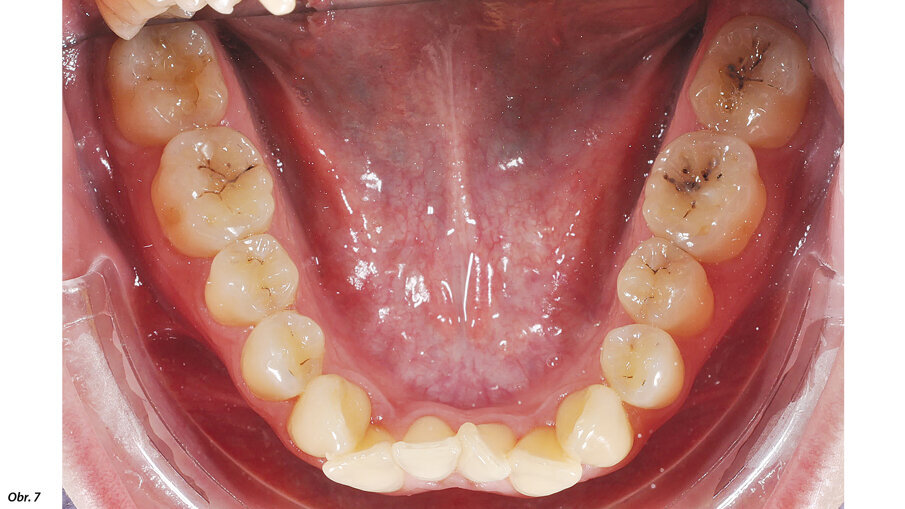

Vyšetřením jsme zjistili výrazný nedostatek místa v horní i dolní frontě. Zub 12, s meziodistální šířkou 6,25 mm, byl eruptován vestibulárně zcela mimo zubní řadu se současným posunem horní středové linie doprava. Mezera mezi zuby 11 a 13 činila 1,5 mm. Nedostatek místa v dolním zubním oblouku činil 2,6 mm resp. 2,85 mm ve dvou dolních kvadrantech. V transverzálním rozměru byl oproti normě menší jak anteriorně, tak i posteriorně. Oproti tomu skus laterálně a v místě špičáků byl normální – zde jsme diagnostikovali I. třídu podle Anglea. Hloubka skusu byla 0,5 mm s tendencí k otevřenému skusu. Incizální schůdek byl 0 mm se skusem hrana na hranu u zubů 11/41 a 21/31/41. Podle Boltnových indexů byl přítomen nepoměr v šířce zubů s přebytkem „zubního materiálu“ v dolní čelisti (obr. 3–5). Při skeletální diagnostice jsme nalezli disharmonii ve velikosti čelistí s retrognátní horní čelistí a ortognátní mandibulou – III. skeletální třída s úhlem ANB -2,3° a hodnotou WITS o velikosti -3,9 mm. U vertikální analýzy byl zřejmý mírně horizontální typ růstu s hodnotou SpP/MeGo 23° a poměrem SGo/NMe 71 % na základě anteriorní inklinace horní čelisti. Interincizální úhel byl lehce zvětšený, což bylo dáno mírnou protruzí horních řezáků spolu s retrudovaným postavením dolních řezáků (obr. 6, 7).

EIntraorální fotografie počátečního stavu pacientky.